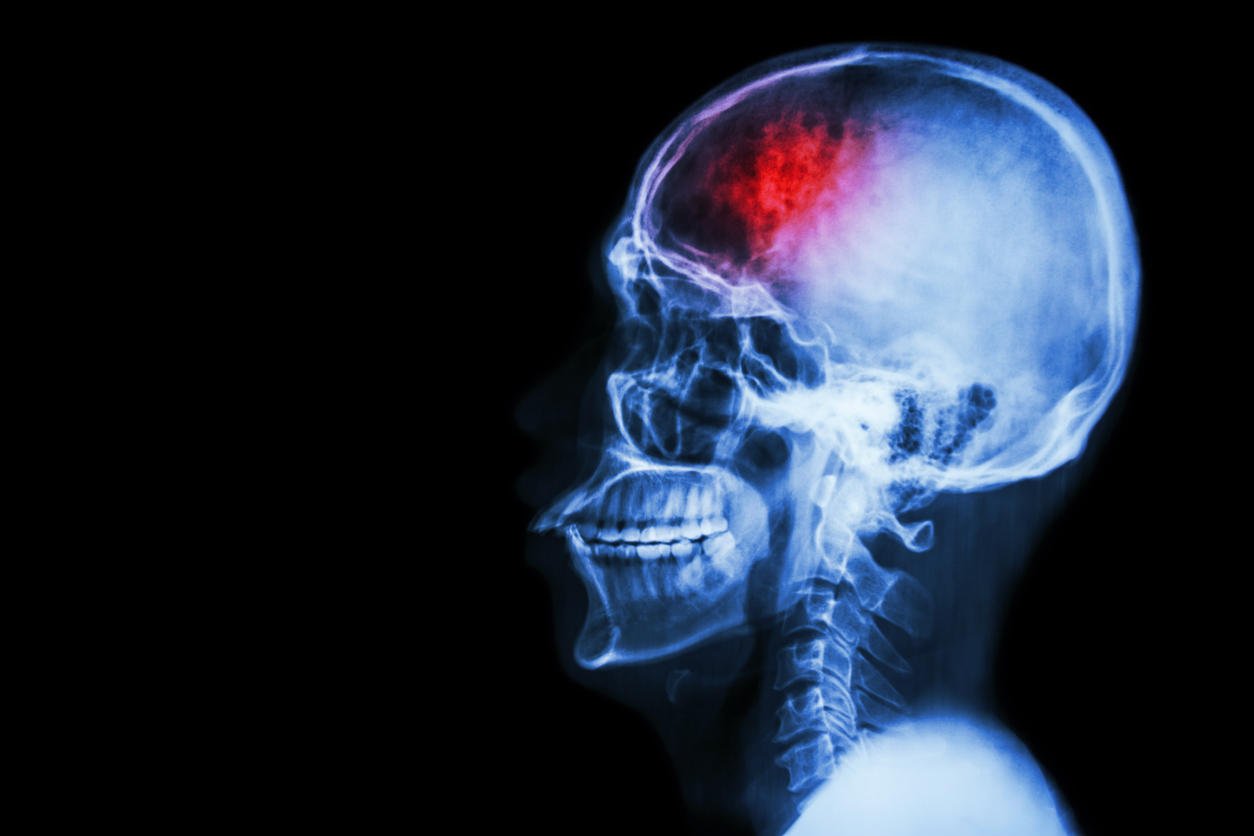

stroke (cerebrovascular accident) film x-ray skull lateral with stroke and blank area at left side

Les caractéristiques d’un AVC silencieux ? Il ne montre aucun signe majeur comparé à un AVC "classique". Il peut alors se répéter et endommager considérablement le cerveau sur du long terme.